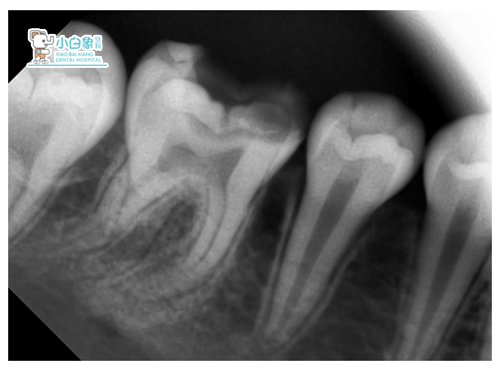

检查:36龋坏达髓腔,探诊疼痛,温度测试疼痛,牙龈无红肿。

X线:低密度影达髓角。

诊断:36慢性牙髓炎。